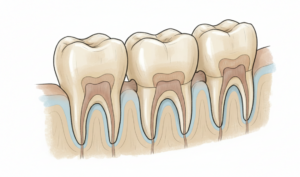

ブリッジは、失った歯の両隣にある健康な歯を「支台歯」として利用し、橋を架けるように人工歯を固定する治療法です。

例えば、1本の歯を失った場合、その両隣の2本を支えにして、計3本分の人工歯を連結した補綴物を装着します。固定式のため取り外す必要がなく、入れ歯と比べて違和感が少ないのが特徴です。

ブリッジは「両隣の歯に依存する」治療法であり、インプラントは「独立して機能する」治療法です。

この構造的な違いが、長期的な安定性や周囲の歯への影響に大きく関わってきます。ブリッジでは健康な歯を削る必要があり、支台歯への負担が避けられません。一方、インプラントは顎の骨に直接固定されるため、他の歯への影響を最小限に抑えられます。